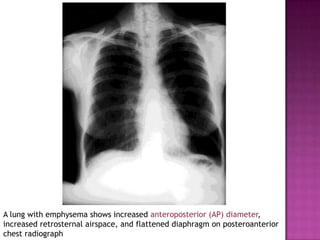

Emphysema : increased AP diameter, increased retrosternal airspace, and

flattened diaphragm on lateral chest radiograph.

A lung with emphysema shows increased anteroposterior (AP) diameter,

increased retrosternal airspace, and flattened diaphragm on posteroanterior

chest radiograph